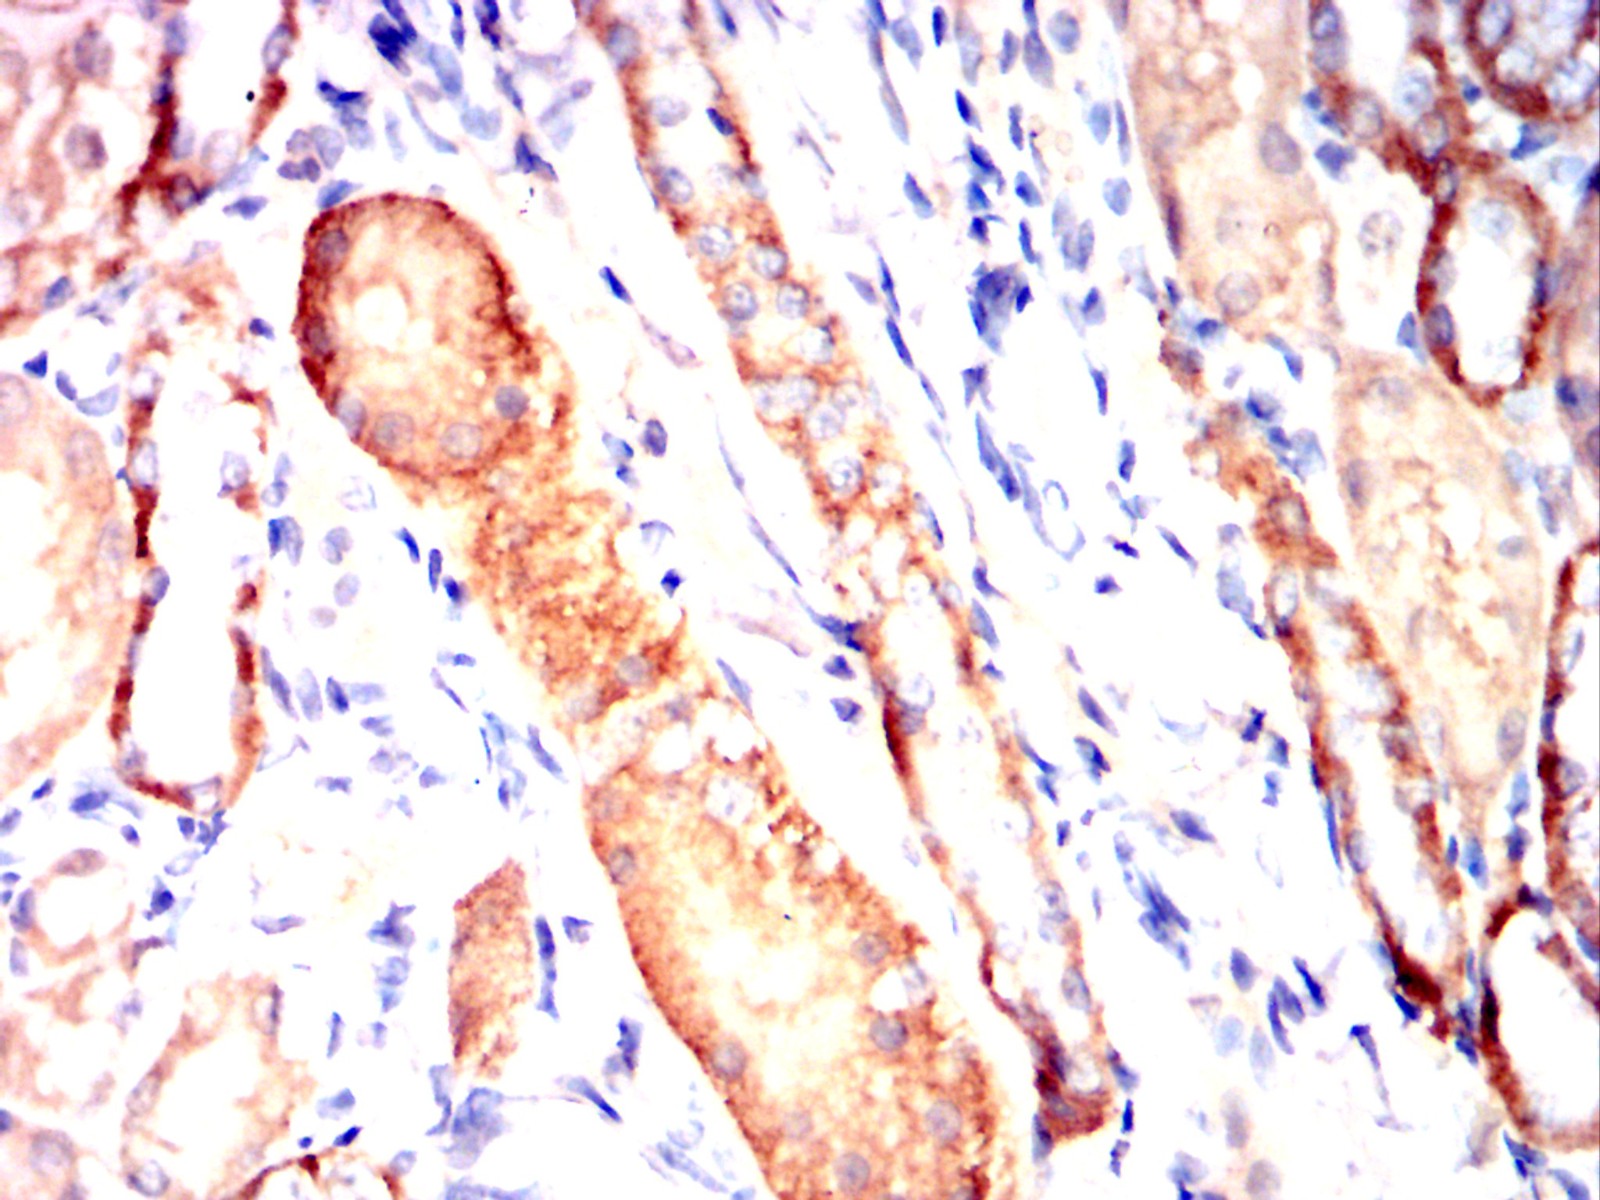

Immunohistochemical analysis of paraffin-embedded human stomach cancer tissues using CD72 mouse mAb with DAB staining.

Immunohistochemical analysis of paraffin-embedded Mouse kidney using CD72 mouse mAb with DAB staining.

Immunohistochemical analysis of paraffin-embedded Rat kidney using CD72 mouse mAb with DAB staining.

Immunohistochemical analysis of paraffin-embedded Rabbit kidney using CD72 mouse mAb with DAB staining.